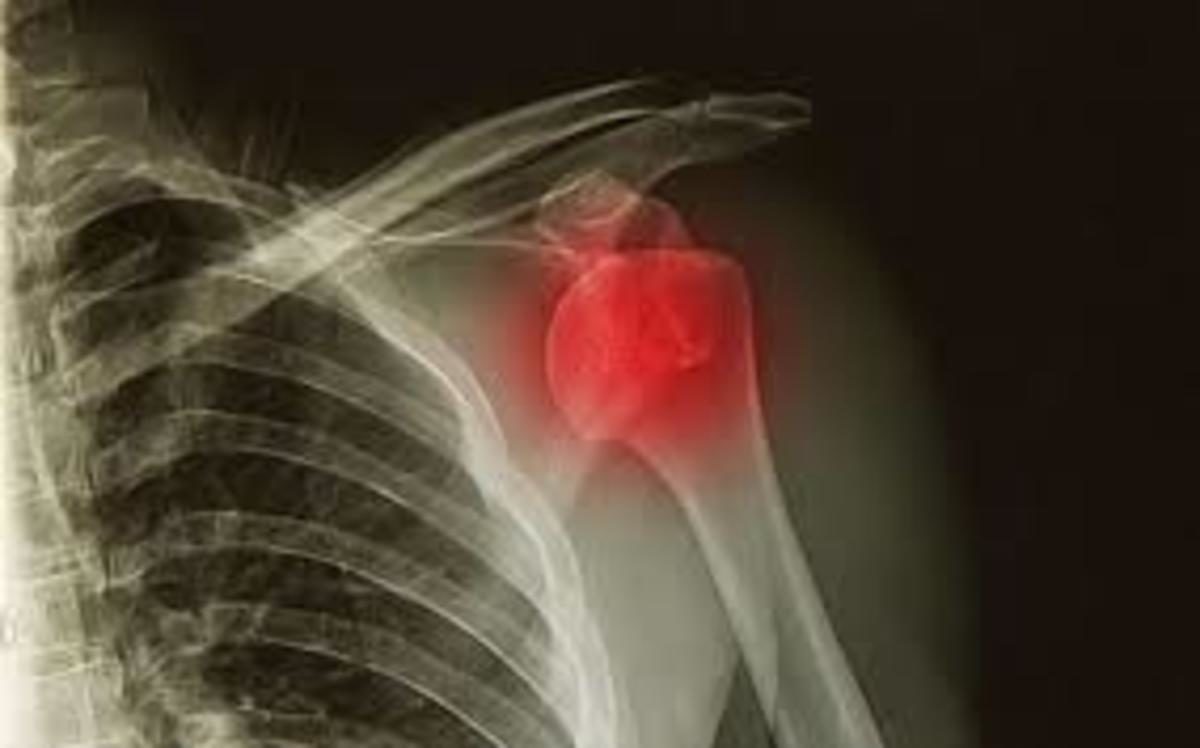

Η εξάρθρωση είναι ένας τραυματισμός των αρθρώσεων με συνέπεια να φεύγουν από κανονικές τους θέσεις. Η αιτία είναι συνήθως τραύμα που προκύπτει από μια πτώση, ένα αυτοκινητιστικό ατύχημα, ή μια σύγκρουση κατά τη διάρκεια της επαφής ή υψηλής ταχύτητας σπορ.

Στους ενήλικες, η πιο συχνή αιτία εξάρθρωσης είναι ο ώμος, στα παιδιά ο αγκώνας.

Η κατάσταση αυτή μπορεί να προκαλέσει ξαφνικό, έντονο πόνο και πρήξιμο. Η εξάρθρωση απαιτεί άμεση ιατρική φροντίδα ώστε να ''μπουν''τα οστά στη σωστή θέση τους.